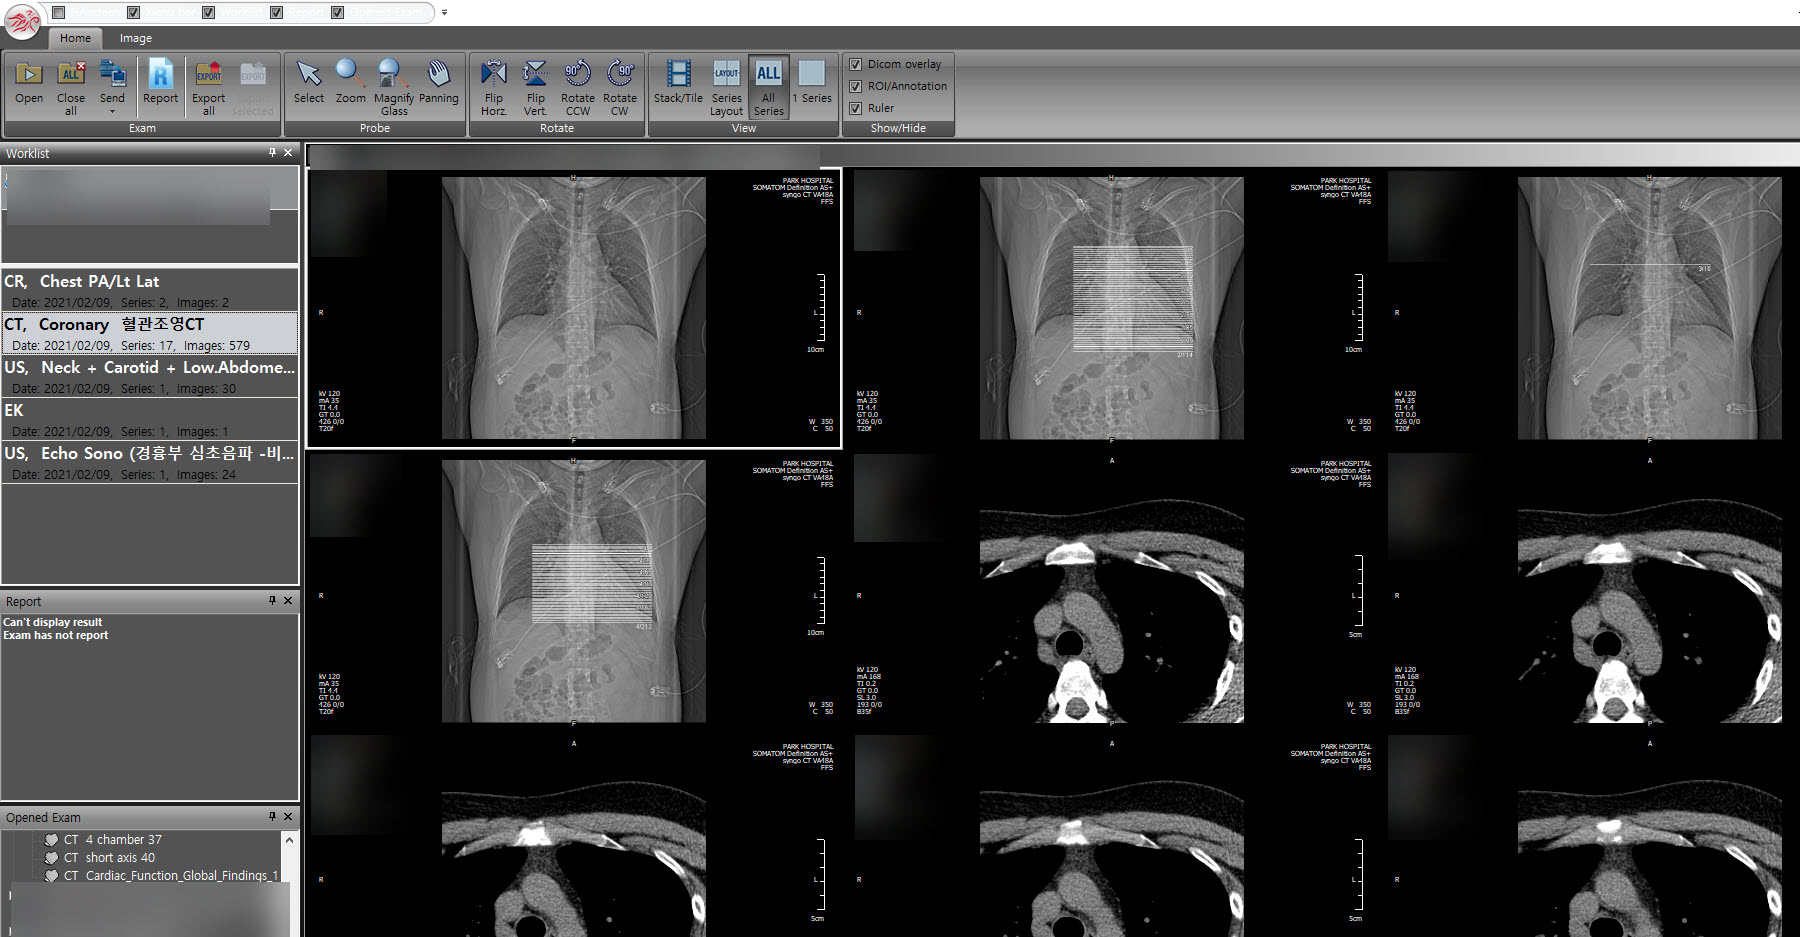

PACS는 CT, MRI와 같은 의료영상장비를 사용하여 촬영된 이미지(DICOM형식)를 저장, 가공, 전송할수있는 시스템이다. 의사는 PACS viewer를 통하여 영상을 판독하고 환자의 상태를 진단할수있다. 다양한 종류의 PACS 뷰어 프로그램이있으며 PacsPlusCV는 PACS 뷰어의 일종이다.

프로그램을 실행하고 의료용 디지털 영상 포맷인 DICOM파일(.dcm)을 불러오기하면 촬영영상 이미지를 확인할수있다.